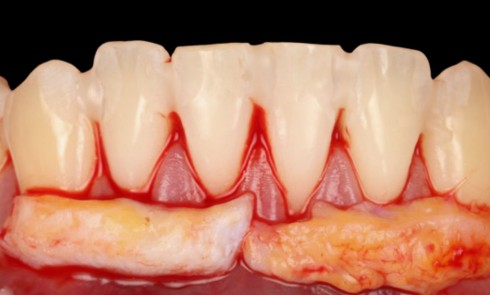

Parodontologie